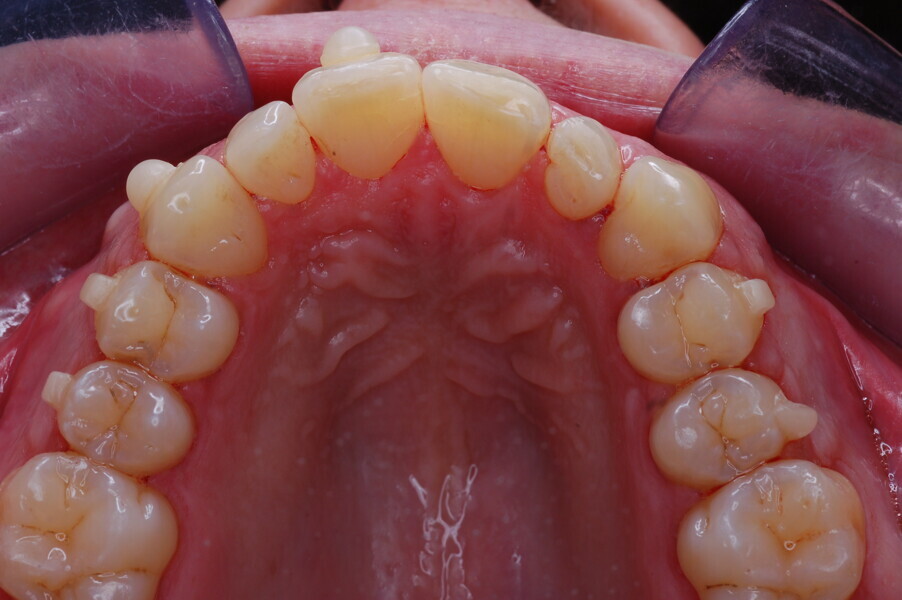

Figs. 1–8: Pretreatment facial and intra-oral photographs.

From the periodontal point of view, the patient showed a good attitude to oral hygiene, but crowding of the mandibular incisors made cleaning difficult in that area, causing plaque accumulation and localised gingival inflammation. The panoramic radiograph revealed the presence of the mandibular third molars and confirmed the absence of the mandibular right central incisor (Fig. 10).

The cephalometric analysis showed a skeletal Class II malocclusion (convexity of Point A: 4.9 mm), a slightly retruded chin position (facial depth: 78.1°) and a skeletal open bite tendency (lower facial height: 53.19°; facial axis: 80.58°; Fig. 9). The mandibular incisors were lingually tipped (Li–APog: 9.3°) and retruded (Li–APog: 1.55 mm), and there was an increased inter-incisal angle of 142.9°.